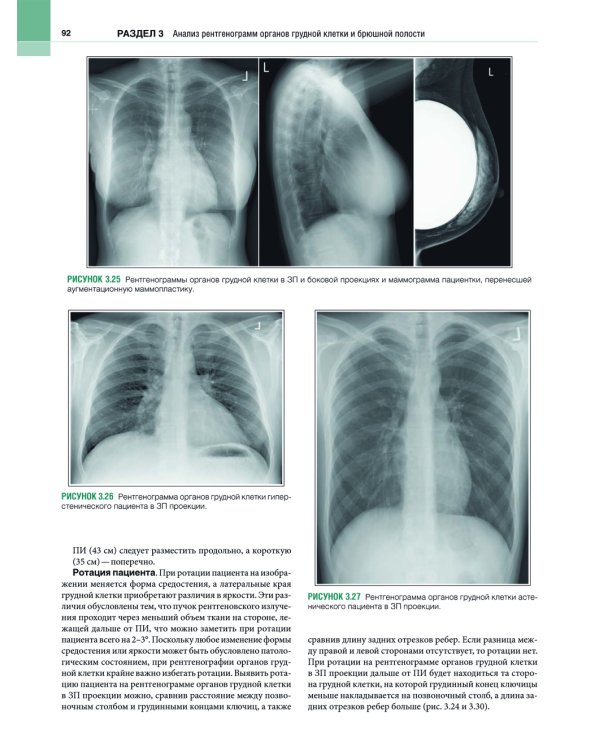

В этом практическом руководстве описаны основные методики выполнения рентгенографии и принципы анализа качества рентгенограмм, стандартные технические параметры исследования, а также варианты укладки и способы их коррекции. Особое внимание уделено базовым принципам получения и цифровой обработки изображений. Для каждой рентгенологической методики приведены фотографии правильной укладки пациента, варианты укладки в нестандартных ситуациях и при определенных патологических состояниях, а также таблицы с сопоставлением вариантов укладки, примеры определения центрального луча или приемника изображения, рисунки и фотографии костных препаратов и условного пациента, позволяющие точнее отобразить взаимное расположение анатомических структур, если проекционное искажение затрудняет интерпретацию рентгенограмм. Издание содержит более 1500 иллюстраций. Книга предназначена для рентгенологов.| Издательство | ИЗД.ПАНФИЛОВА |